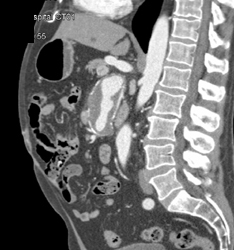

Diagnosis

Ulceration W/o Abscess